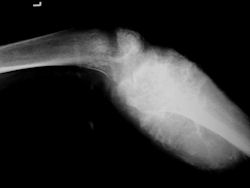

Proximal Humerus: Radical Limb Sparing Extra-Articular Resection and Prosethetic Reconstruction

Gross Pathology: Osteosarcoma of Proximal Humerus

- originates from metaphysis of the proximal humerus, extends into surrounding soft tissues

- large soft tissue component that is crossing the glenohumeral joint

- was removed via an extra-articular resection, including scapula (Tikhoff-Linberg resection)

Examples of radical limb sparing surgeries for osteosarcomas in various anatomic locations (distal femur, proximal tibia, proximal humerus, scapula)

In each case, the tumor and bone from which it arose were resected. This required meticulous dissection, mobilization and preservation of adjacent pertinent neurovascular structures. In each case presented here, the defect was reconstructed with a special modular segmental tumor prosthesis. This also replaces the adjacent joint in many instances.